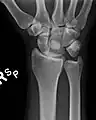

![]() The left lunate bone | |

The lunate is a crescent-shaped carpal bone found within the hand. The lunate is found within the proximal row of carpal bones. Proximally, it abuts the radius. Laterally, it articulates with the scaphoid bone, medially with the triquetral bone, and distally with the capitate bone. The lunate also articulates on its distal and medial surface with the hamate bone.[2]: 708 [3]

Bone

The proximal surface of the lunate bone is smooth and convex, articulating with the radius. The lateral surface is flat and narrow, with a crescentic facet for articulation with the scaphoid bone. The medial surface possesses a smooth and quadrilateral facet for articulation with the triquetral bone. The palmar surface is rough, as is the dorsal surface. The dorsal surface is broad and rounded. The distal surface of the bone is deep and concave.[4]